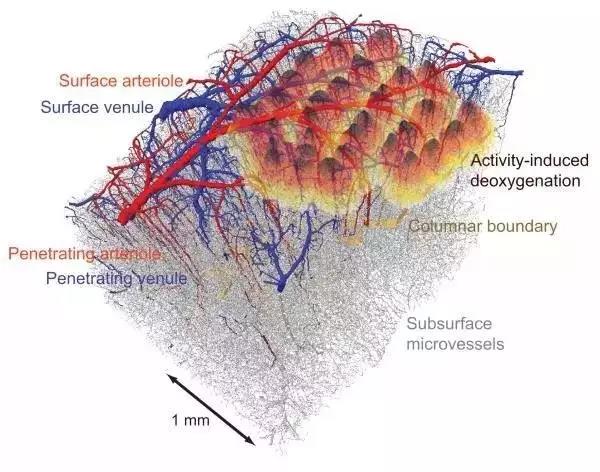

最后,還有血管。在每立方毫米的皮質,共有一米的毛細血管。在我們的規模下看,這意味著在我們的立方米內,有一公里長的血管。這樣大小的空間內,血管是什么樣子?

最后,還有血管。在每立方毫米的皮質,共有一米的毛細血管。在我們的規模下看,這意味著在我們的立方米內,有一公里長的血管。這樣大小的空間內,血管是什么樣子?